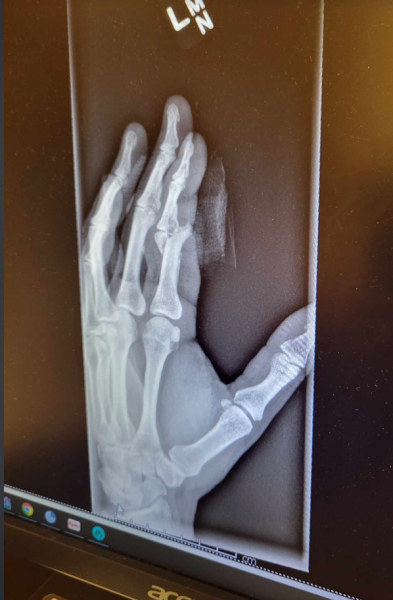

Just don't do this!

A buddy just sent me this. This is 2 weeks post surgery. He got his finger in the way of a splitter helping a buddy split wood.

That is a pin holding the bones together to heal. It will be removed once healed.

When it first happened he captioned these photos with, "apparently I'm not as good with this whole wood splitting thing as you are". LOL He said the finger was just hanging.